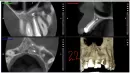

Сделала еще один снимок. Врач мне сказала ходить с открытыми каналами и 2 раза в неделю протирала каналы ватой с иглой. Это продолжалось 2 месяца и мне становилось все хуже и хуже. Затем я сменила врача и в декабре мне несколько раз ставили в каналы препарат Эндофил и 4 февраля запломбировали зуб Эндофилом. Стало легче, но больно конца не пошла. Сейчас на этих зубах установлена временная пломба дентин порошок. Сделала КТ. На данный момент меня беспокоит болезненность при надкусывании. Больно прикасаться к лицу под носом с левой стороны. Больно, когда врач стучит по этим зубам, особенно по 21 зубу.

В 21-ом зубе канал заполнен не полностью, а в 22-ом материал за апексом. Рекомендуем, пройти перелечивание, с закладкой кальция и наблюдением в течение полугода.